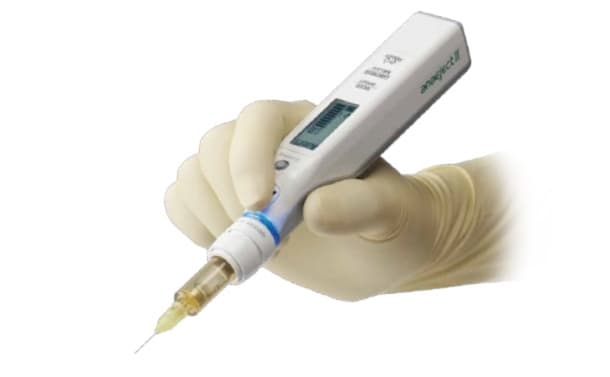

電動注射器

コンピューターチップで注入時の圧力をコントロールし、刺す瞬間の痛みを和らげることができる注射器です。

当院では表面麻酔と電動注射器を併用し、痛点の少ない箇所から数回に分けて麻酔することで、患者様への痛みのストレスを少なくするよう心がけています。